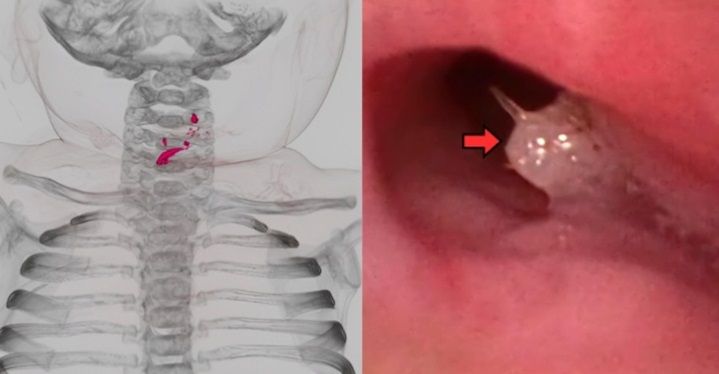

살아 있는 물고기를 삼킨 7개월 아기의 CT 검사에서 목 부위 이물질(빨간색)이 보이는 모습. 오른쪽 사진은 내시경 검사를 통해 이물질이 확인된 모습. 출처=Trauma & Case Reports, 코메디닷컴

상급병원에서 검사한 결과, 기관지에 물고기로 추정되는 백색 이물질이 있었고 식도에 가시 2개가 박혀 있었다. 이 밖에 물고기 가시, 비늘로 추정되는 여러 개의 이물질이 있었고 이로 인해 식도가 찢어지고 구멍이 난 상태였다.